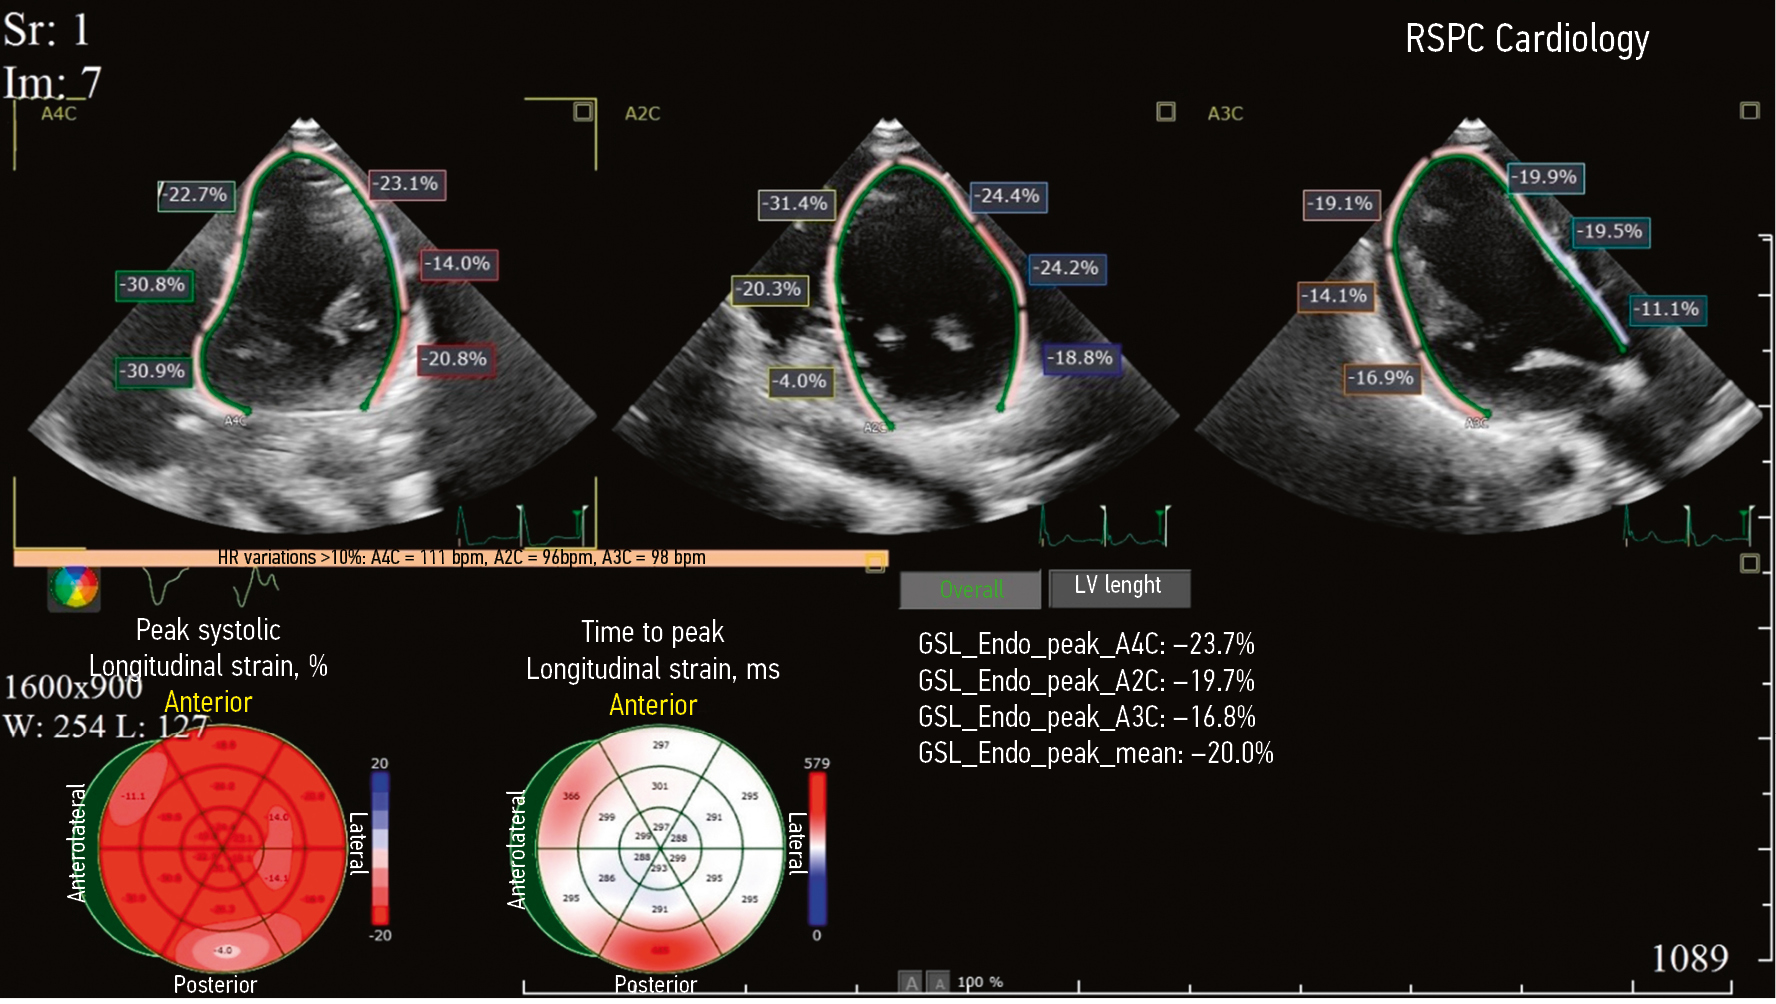

Принимая во внимание клиническую картину заболевания, результаты лабораторно-инструментальных исследований, пациентку повторно госпитализировали в кардиологическое отделение в сентябре 2024 г. для выполнения ЭЭФИ и определения дальнейшей тактики ведения. По данным ЭхоКГ, определена ФВ ЛЖ 56%, гипокинез базального передне-перегородочного и базального перегородочного сегментов ЛЖ; полости сердца не расширены. При выполнении 2D-Strain ЭхоКГ не выявлено снижения глобальной продольной деформации ЛЖ (GLS — –20,0%) (риc. 4). По данным ЭЭФИ, зафиксировано удлинение интервала HV — 86 мс (рис. 5).

Рис. 4. 2D-Strain эхокардиография пациентки К. Глобальная продольная деформация левого желудочка –20,0%.